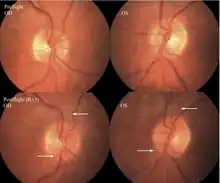

The first U.S. case of visual changes observed on orbit was reported by a long-duration astronaut that noticed a marked decrease in near-visual acuity throughout his mission on board the ISS, but at no time reported headaches, transient visual obscurations, pulsatile tinnitus or diplopia (double vision). His postflight fundus examination (Figure 1) revealed choroidal folds below the optic disc and a single cotton-wool spot in the inferior arcade of the right eye. The acquired choroidal folds gradually improved, but were still present 3 year postflight. The left eye examination was normal. There was no documented evidence of optic-disc edema in either eye. Brain MRI, lumbar puncture, and OCT were not performed preflight or postflight on this astronaut.[5]

The seventh case of visual changes associated with spaceflight is significant in that it was eventually treated postflight. Approximately 2 months into the ISS mission, the astronaut reported a progressive decrease in his near and far acuity in both eyes. The ISS cabin pressure, CO2 and O2 levels were reported to be within normal operating limits and the astronaut was not exposed to any toxic substances. He never experienced losses in subjective best-corrected acuity, color vision or stereopsis. A fundus examination revealed a grade 1 bilateral optic-disc edema and choroidal folds (Figure 15).[5]